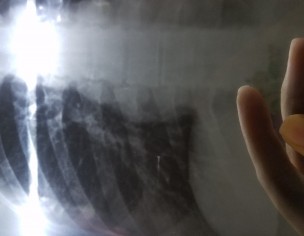

Is this shadow in my chest xray something to worry about? The doctor I consulted said that it is an xray defect though I do feel pain in the right side of my chest.

It’s foreign body particle probably. Plz repeat XRay and check pulmonologist.